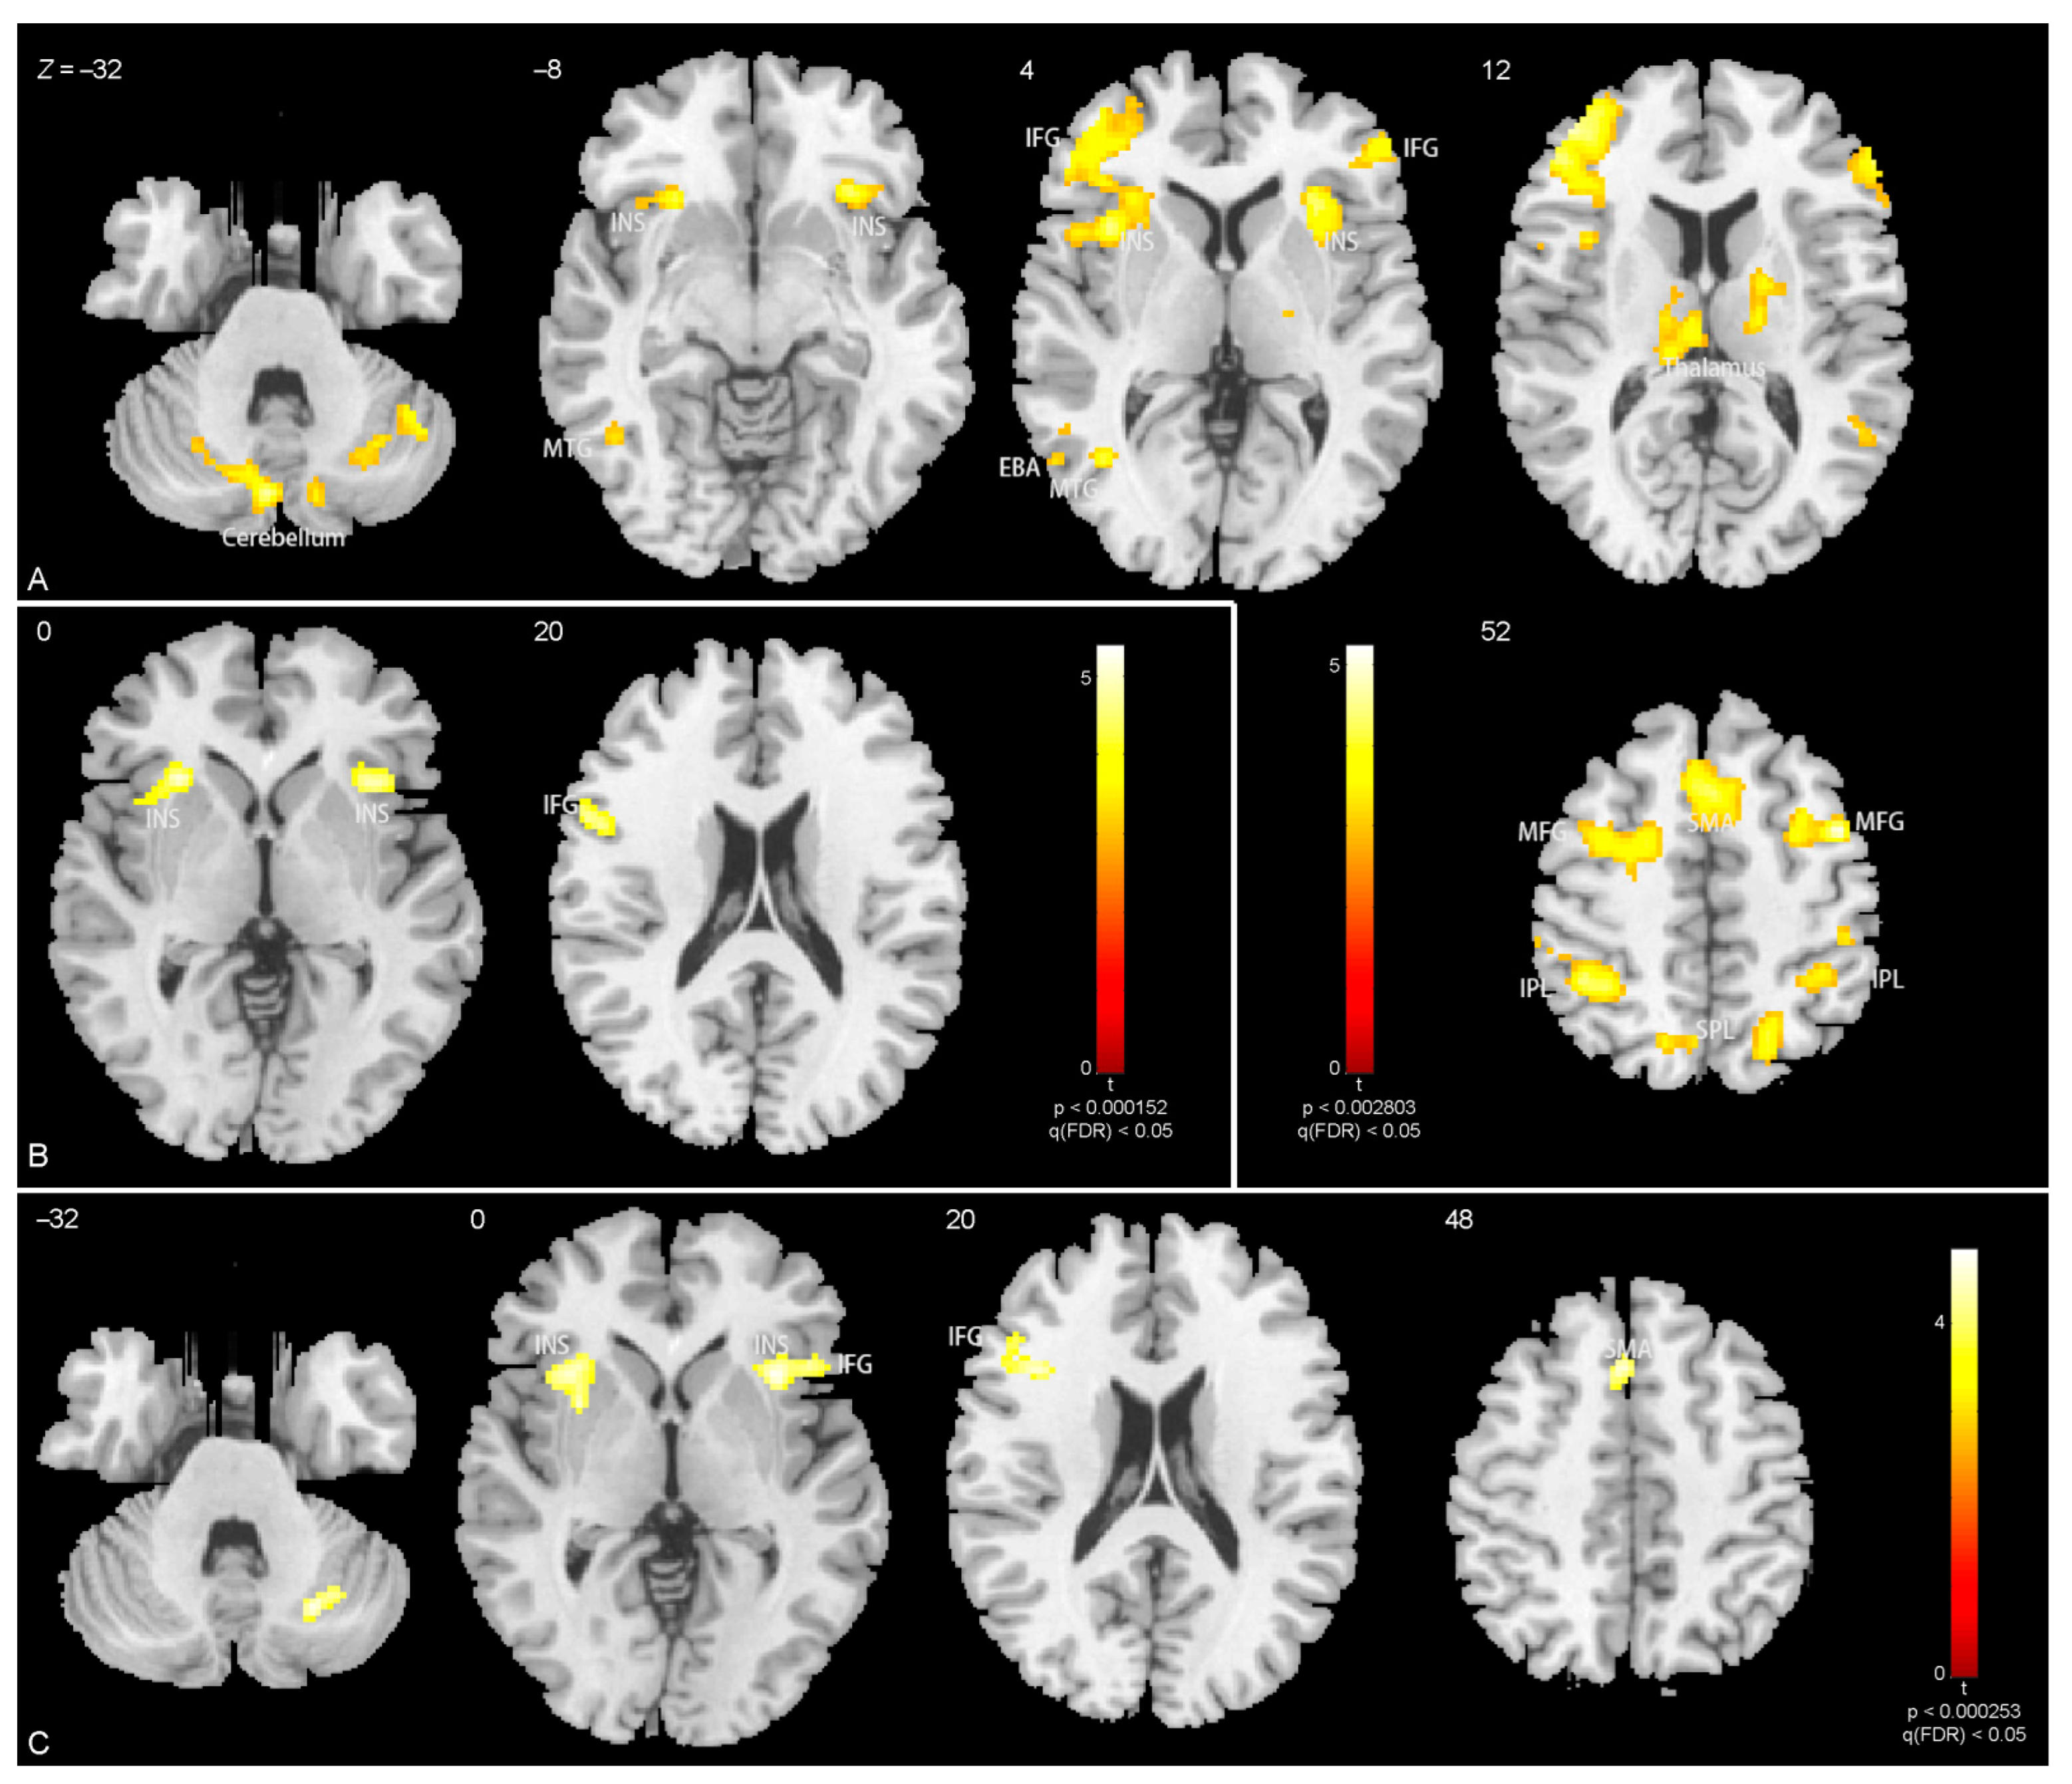

3.3. Brain Activations

| In whole body, | ||||||

| Anger > neutral | ||||||

| L occipito-temporal gyrus (EBA) | −48 | −76 | −2 | 4.3 | 0.015 | 25 |

| Fear > neutral | ||||||

| L occipito-temporal gyrus (EBA) | −54 | −60 | 12 | 5.2 | 0.010 | 35 |

| In torso with arms, | ||||||

| R lingual gyrus | 20 | −84 | 6 | 5.4 | 0.032 | 80 |

| L occipito-temporal gyrus (EBA) | −50 | −74 | 0 | 4.6 | 0.048 | 60 |

| R middle temporal gyrus | 50 | −62 | 8 | 4.6 | 0.045 | 23 |

| L occipito-temporal gyrus (EBA) | −54 | −62 | 10 | 4.6 | 0.012 | 24 |

| In legs, | ||||||

| R cerebellum | 44 | −56 | −34 | 4.4 | 0.010 | 212 |

| L cerebellum | −12 | −70 | −36 | 4.7 | 0.0038 | 285 |

| L middle temporal gyrus | −42 | −60 | 4 | 4.0 | 0.0053 | 259 |

| L insula | −30 | 22 | −2 | 5.2 | 2.6 × 10−16 | 3593 |

| R insula | 32 | 20 | 0 | 4.8 | 4.6 × 10−4 | 435 |

| R middle frontal gyrus | 42 | 4 | 52 | 5.0 | 3.1 × 10−9 | 1557 |

| R thalamus (including R caudate) | 20 | −4 | 14 | 3.9 | 0.016 | 185 |

| L thalamus (including L caudate) | −6 | −18 | 12 | 3.9 | 0.0091 | 223 |

| R inferior parietal lobule | 68 | −34 | 24 | 3.8 | 0.019 | 171 |

| L inferior parietal lobule | −32 | −42 | 42 | 4.9 | 2.8 × 10−8 | 1297 |

| R inferior parietal lobule | 32 | −42 | 44 | 4.4 | 5.2 × 10−5 | 604 |

| L(R) supplementary motor area | −6 | 20 | 50 | 4.5 | 3.3 × 10−6 | 841 |

| L(R) precuneus | −14 | −68 | 56 | 4.1 | 0.023 | 159 |

| R superior parietal lobule | 18 | −64 | 54 | 4.0 | 0.0028 | 310 |

| L insula | −30 | 22 | −4 | 5.4 | 5.4 × 10−5 | 273 |

| R insula | 34 | 20 | 2 | 5.0 | 7.1 × 10−4 | 173 |

| L inferior frontal gyrus | −56 | 10 | 22 | 4.7 | 0.0090 | 97 |

| In head, | ||||||

| - | − | − | − | − | − | − |

| R cerebellum | 24 | −66 | −32 | 4.6 | 0.042 | 70 |

| R insula, R inferior frontal gyrus | 32 | 18 | 0 | 4.6 | 1.7 × 10−4 | 282 |

| L insula | −34 | 20 | −2 | 4.6 | 0.0020 | 177 |

| L inferior frontal gyrus | −42 | 18 | 16 | 4.8 | 0.0032 | 142 |

| L supplementary motor area | −6 | 22 | 44 | 4.7 | 0.0020 | 164 |